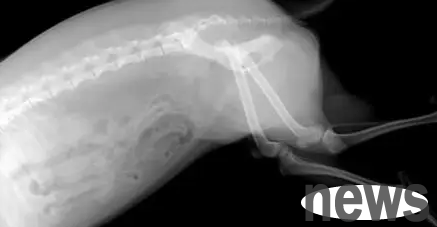

If the dog is seriously injured, such as fractures, bone cracks, lacerations, internal organ damage, etc., the probability of self-healing is not very high, and it needs to be taken to a pet hospital for treatment. Depending on the severity, whether surgery is needed. In addition, if the dog's wound is large and deep, it will not heal on its own. The dog needs to be treated immediately around the wound and on the wound surface, otherwise it is likely to cause serious infection and even threaten the dog's life.